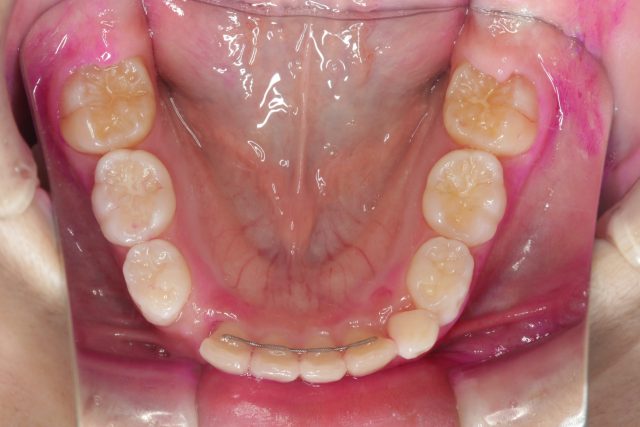

8歳男の子インビザラインファースト:永久歯スペース不足を解消

| 年齢・性別・主訴 | 8歳男の子 永久歯が並ぶスペースが足りない |

| 治療方法 | インビザラインファーストを使用し(1日20時間以上の着用) 、問題点の改善を行なった。 |

他のAfter